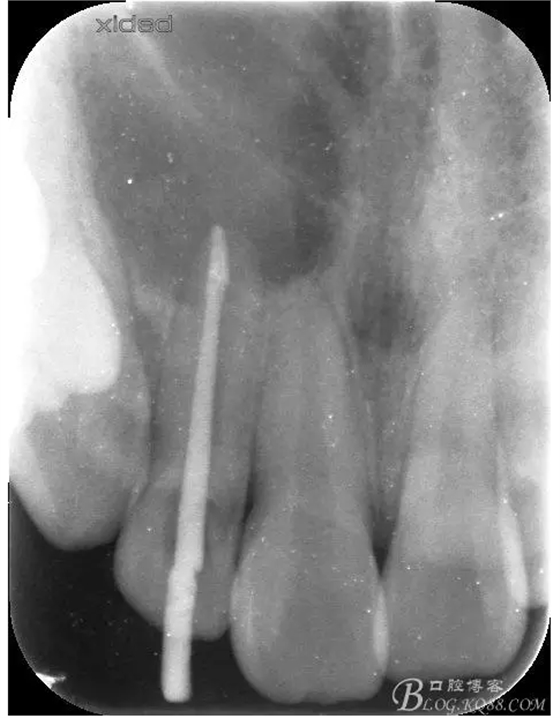

1.術前的根尖片檢查及根管治療影像: